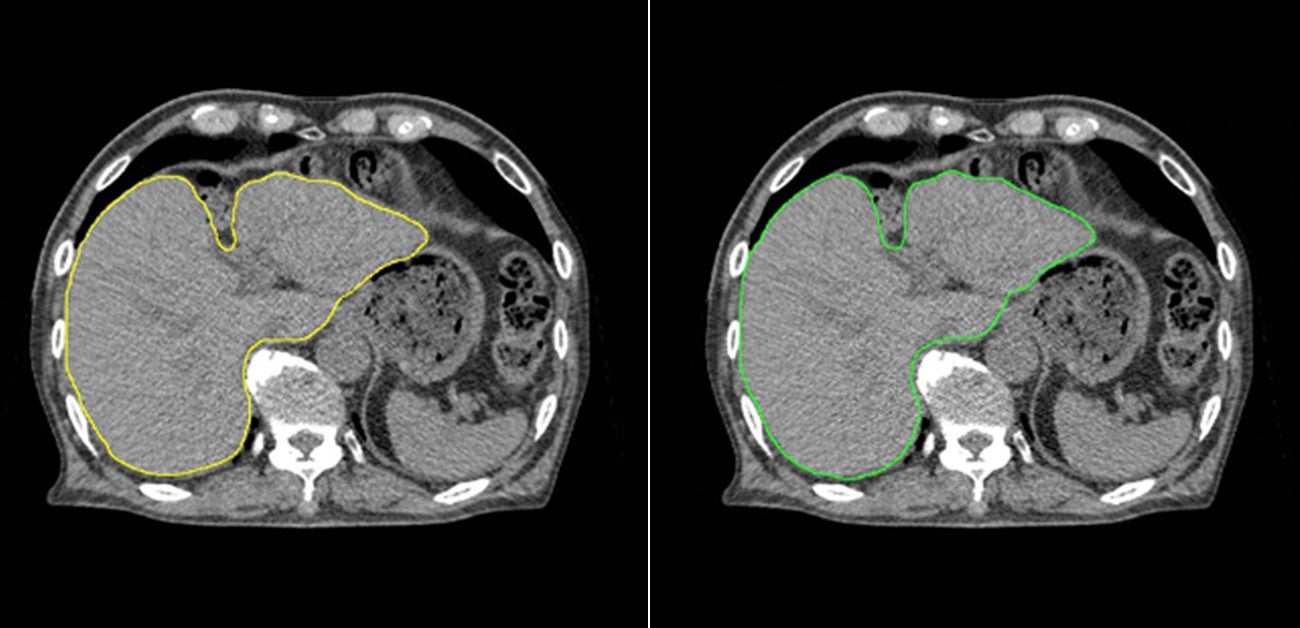

肝臓モデルを使用した例では、輪郭作成に要する時間は、従来の手作業のみでは30分以上要したものが、臨床利用ための人による修正時間も含め、Ai-Segによる自動輪郭作成及び必要に応じての軽微な修正作業を合わせて5分程度までに短縮することができました。図1に示すように医師とAi-Segが作成した輪郭を比較しても違いがわからないほどの水準にまで達しています。

図の上は前立腺、下は肝臓のCT画像。左はAi-Segによる自動抽出、右は医療従事者の手入力による抽出。Ai-Segによる描画は医療従事者による描画と遜色ない精度で輪郭を自動作成が可能(図の提供:大阪大学プレスリリースより※)